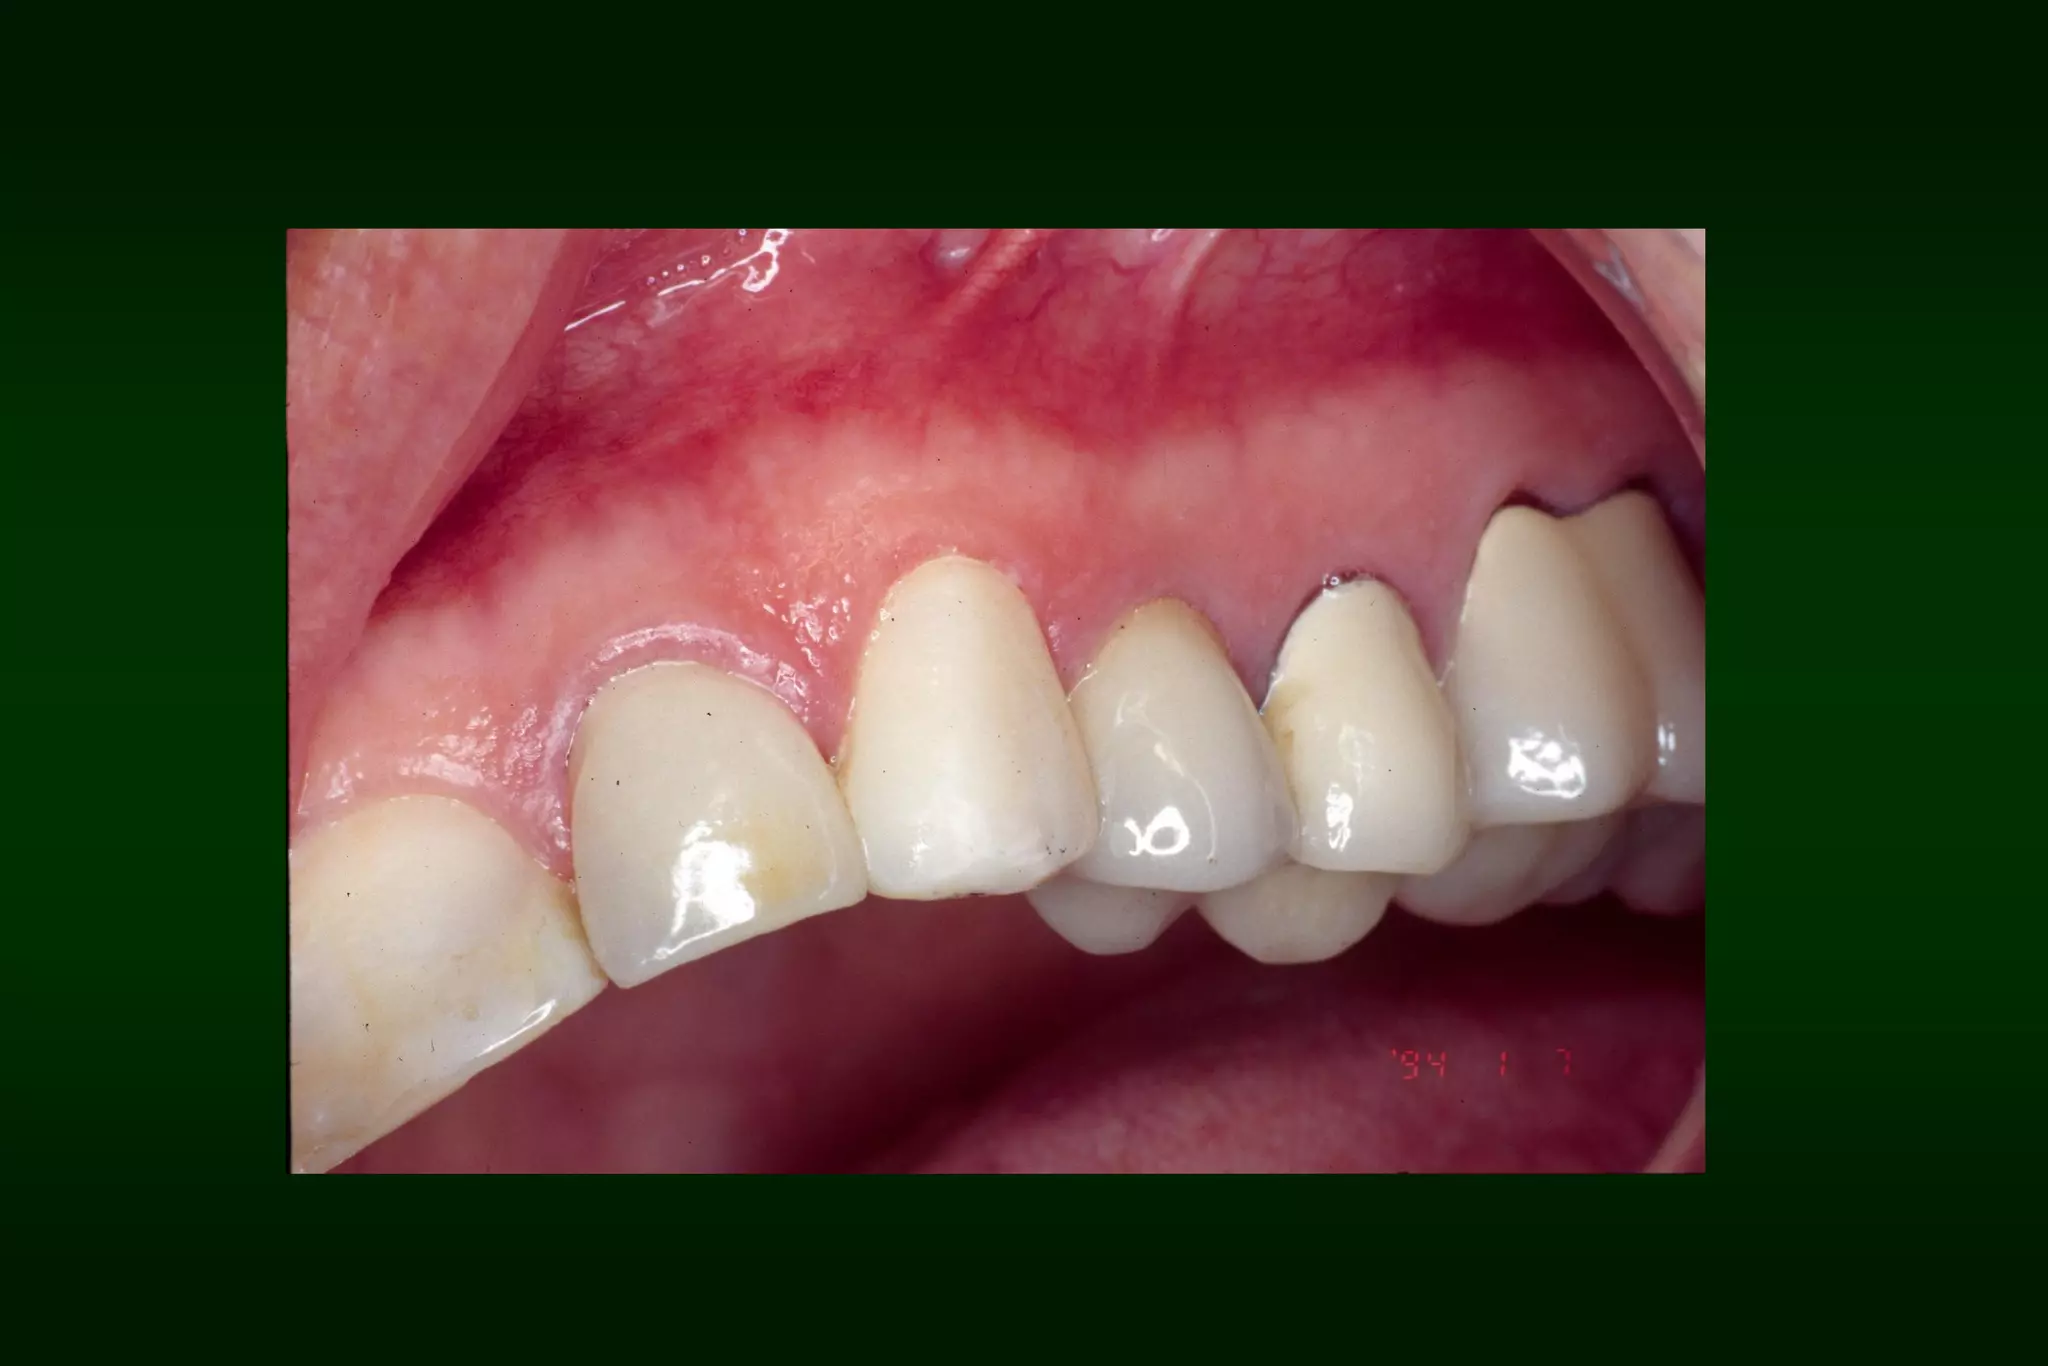

After 1 week

After 2 months